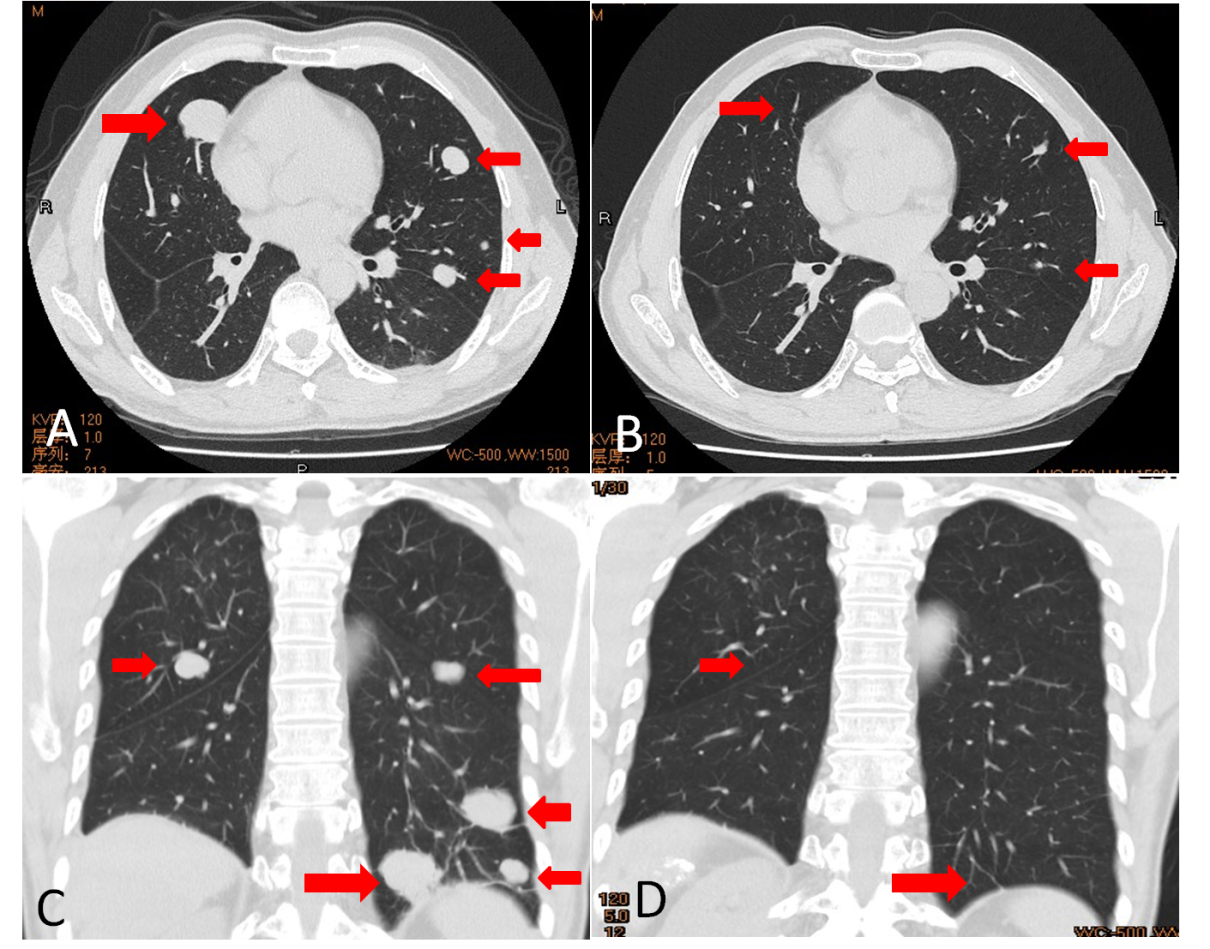

A,C为阿帕替尼治疗前,B,D为阿帕替尼治疗6月后

病例展示:一50岁男性,有慢性乙肝病史,AFP:2213ng/mL。胸腹部CT提示:肝内肿物伴双肺多发转移。肺肿物穿刺病理示:肝细胞癌。给予TACE联合索拉非尼治疗,治疗后复查提示:肺内病灶持续增大,增多,AFP持续增高。考虑索拉非尼抵抗无效,然后改用阿帕替尼治疗,经阿帕替尼治疗后病灶持续缩小,AFP持续下降,6个月后复查肺内病灶几乎全部消失。该患者对阿帕替尼响应良好,最后总生存期达38月。